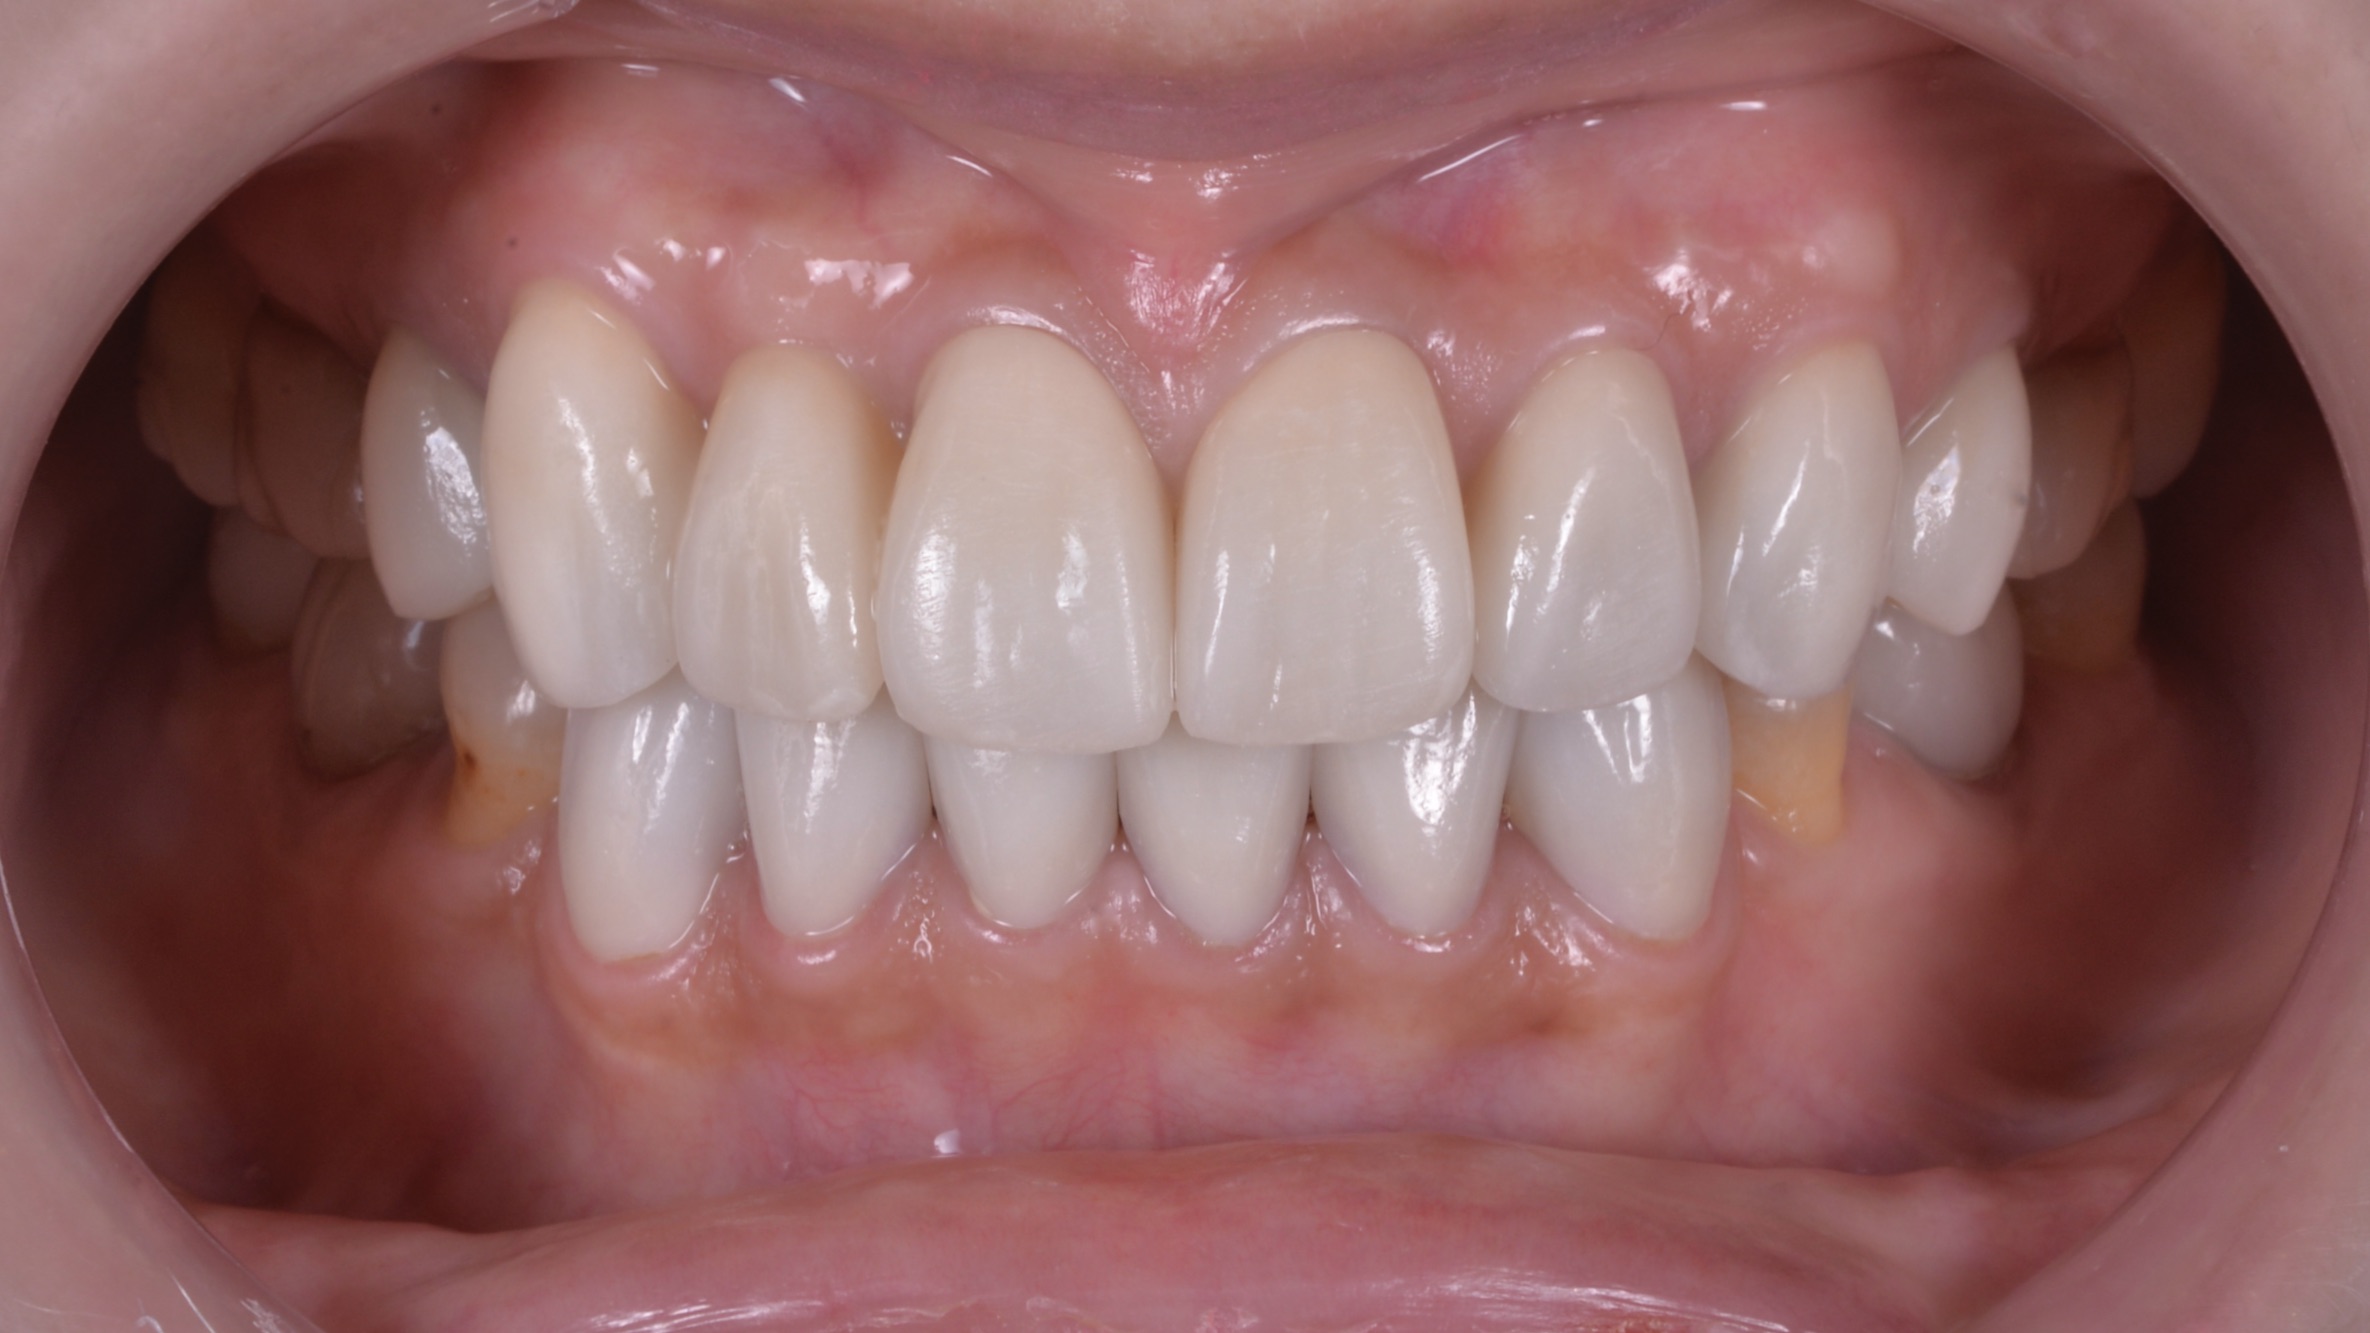

患者自身でもいくどとなく再現ができる適切な噛み合わせのポジションで前歯しっかり噛ませることができました!

変色した歯もセラミックで改善!

前歯のインプラントもどこに入っているかわかりません。